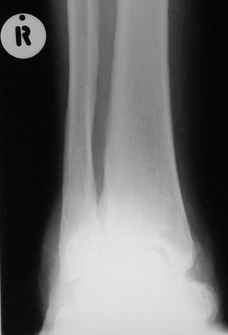

Уажаемые коллеги,представленные рентгенограмммы я показывал на нашем х-рей митинге - они были встречены с большим интересом.. Ну, ещё бы - я сам эту патологии встречал раза три за всю свою долгую жизнь:

VR> Кто шустрый - при какой патологии встречается так называемые <суставы Шарко>?

Сирингомиелия,

Травма спинного мозга

Опухоль

Т.н. нейрогенная артропатия бвает при диабете, периферических нейропатиях, заболеваниях спинного мозга... Как-то довелось вести больного с таким поражением тазобедренных суставов при третичном сифилисе.